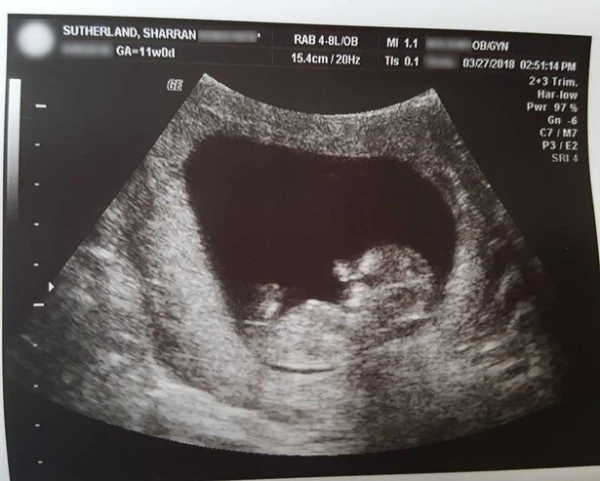

Sharran Sutherland, de Fair Grove, Missouri (Estados Unidos), es la madre de 40 años que perdió a su hijo Miran de 14 semanas de gestación, luego de que las ecografías indicarón que su corazón había dejado de latir.

Ecografía de Miran - Foto: Cortesía Sharran Sutherland